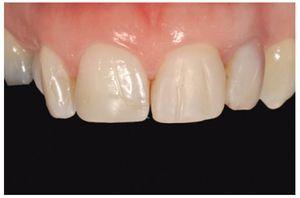

Figura 1 Paciente de 16 años de edad con una restauración deficiente en el diente número 11 y una erupción pasiva evidente.